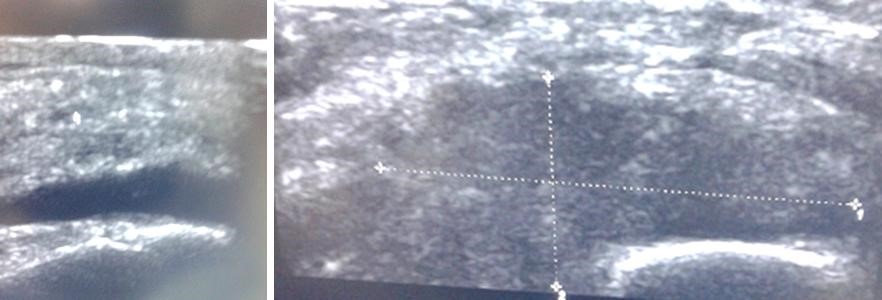

Volver a los detalles del artículo Sinovitis vellonodular pigmentada difusa